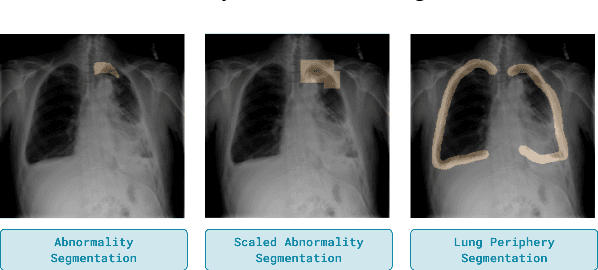

Abstract:Domain generalization in medical image classification is an important problem for trustworthy machine learning to be deployed in healthcare. We find that existing approaches for domain generalization which utilize ground-truth abnormality segmentations to control feature attributions have poor out-of-distribution (OOD) performance relative to the standard baseline of empirical risk minimization (ERM). We investigate what regions of an image are important for medical image classification and show that parts of the background, that which is not contained in the abnormality segmentation, provides helpful signal. We then develop a new task-specific mask which covers all relevant regions. Utilizing this new segmentation mask significantly improves the performance of the existing methods on the OOD test sets. To obtain better generalization results than ERM, we find it necessary to scale up the training data size in addition to the usage of these task-specific masks.